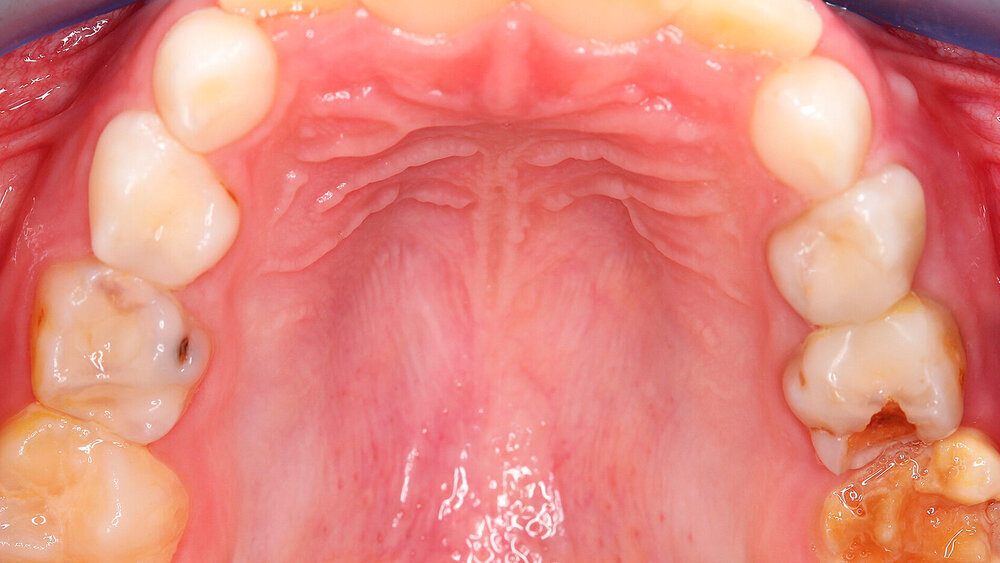

Der Begriff der „Molaren-Inzisiven-Hypomineralisation“ hat vor knapp 20 Jahren Eingang in die Literatur gefunden [Weerheijm et al., 2001]. Beschrieben wird eine systemisch bedingte Hypomineralisation von ein bis vier bleibenden ersten Molaren mit oder ohne Beteiligung der Inzisiven (Abbildungen 1 und 2).

Die Ausprägung der Mindermineralisation kann stark variieren (Abbildungen 3 und 4). Klinisch zeigen sich an den betroffenen Zähnen unterschiedlich starke Verfärbungen beziehungsweise Opazitäten bis hin zu ausgeprägten Schmelzverlusten. So kann die Mineralisationsstörung im Bereich der Molaren auf einzelne Bereiche beschränkt sein, das Fissurenrelief einbeziehen oder sich über die gesamte Glattfläche erstrecken [Koch et al., 1987]. Bei den Inzisiven ist die Mindermineralisation bukkal zu finden. Geringgradig betroffene Zähne sind dabei eher durch weiß-gelbliche oder gelb-braune, unregelmäßige Verfärbungen gekennzeichnet, schwere Hypomineralisationsformen weisen dagegen abgesplitterte oder fehlende Schmelz- und/oder Dentinareale unterschiedlichen Ausmaßes auf.